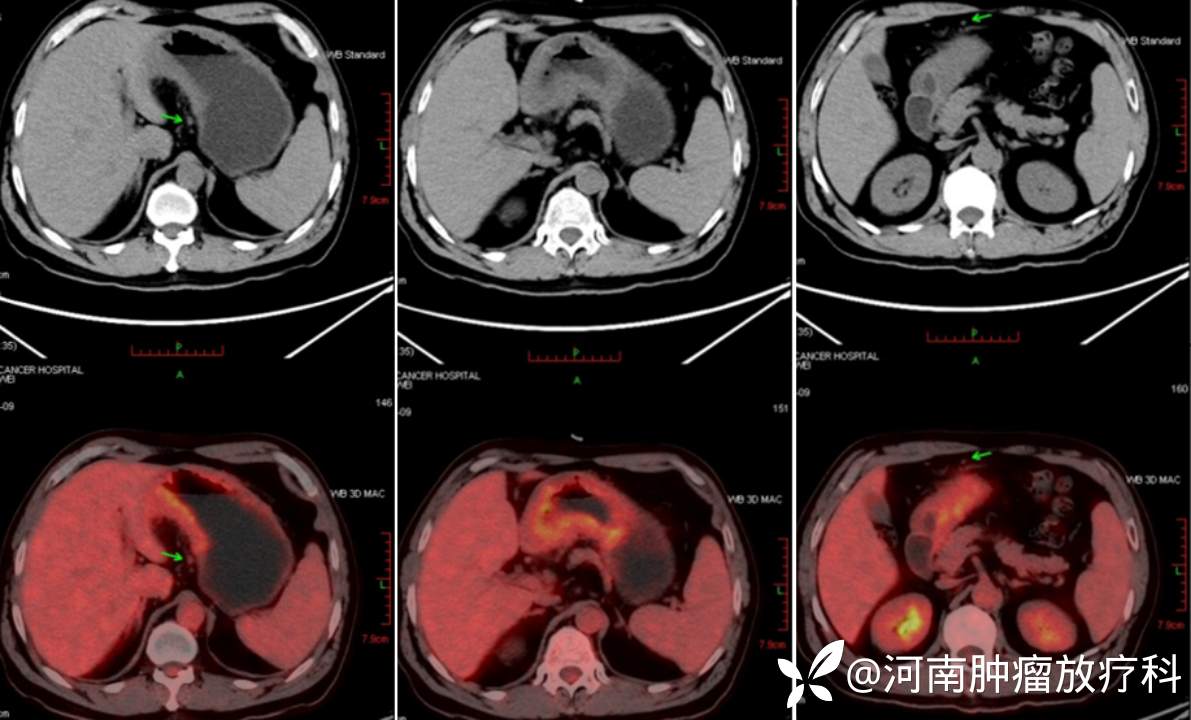

CT:2022.09.12(颈部至盆腔):胃壁增厚,粘膜层强化明显,胃窦显著。胃窦周围多发小淋巴结。

PET-CT(2022.9.12):胃体小弯侧及胃窦不均匀增厚,代谢高,符合胃癌表现。腹腔、肝胃间及胃壁周围多发软组织结节影,淋巴结转移不除外。余未见明显异常。